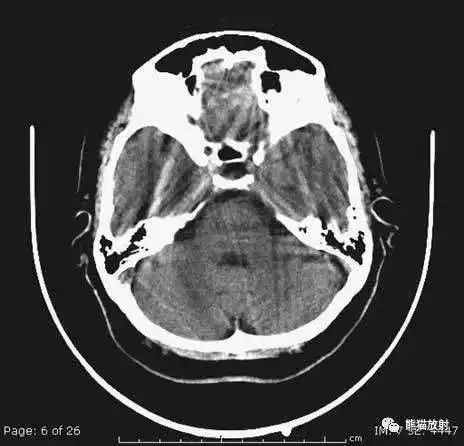

应注意的常见伪影

常见于颅脑基底部及后颅窝

层厚较大时,可导致血液密度表现,在脑基底部较典型,易发生在眼眶上方额叶。

本例表现:四脑室囊性病变导致梗阻性脑积水。